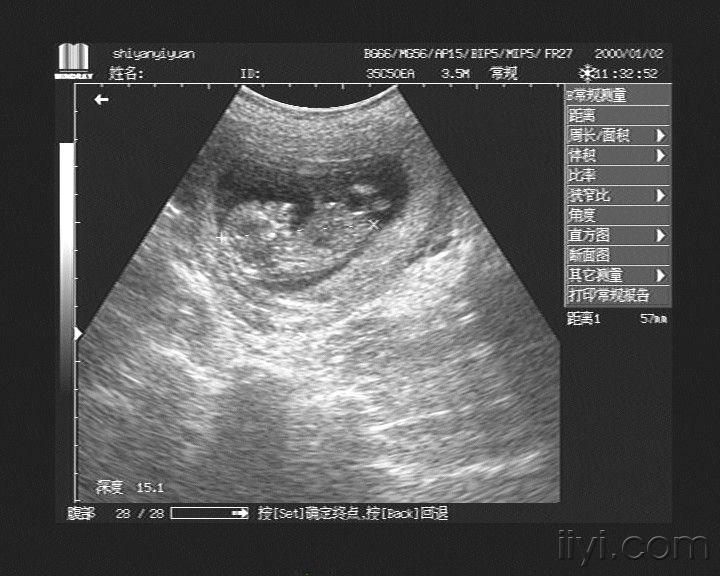

怀孕12周彩超图

怀孕12周彩超图,怀孕12周男孩孕彩超图

第12周彩超,第一次看到宝贝的模样了!

孕12周产检,小宝宝像个小老头躺着呢,头

孕12周,感觉好像能看见胎儿的鼻子,做彩超

孕12周胎儿畸形

今天十二周三维彩超,能知道男孩女孩吗?宝妈们